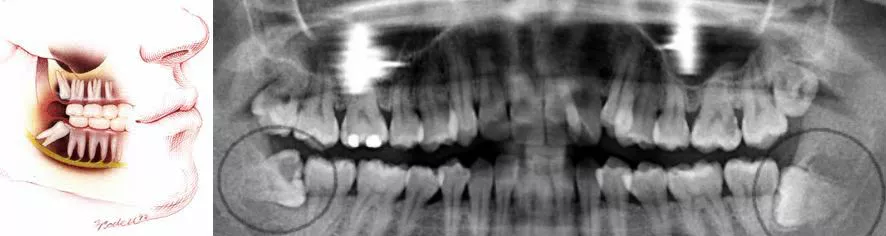

Wisdom teeth become a problem as they begin to grow most commonly in patients that do not have enough space at the rear of the jaw to fit them. If this happens, the teeth become wedged in behind the tooth in front (impacted). Impacted wisdom teeth can cause a variety of problems including infection, pain, damage to nearby molars, and food packing which can then lead to decay.

If the dentist deems it necessary for you to have your wisdom teeth out, you can choose to have the surgery done here at our clinic or be referred to an Oral Surgeon. For those who opt to get it done here we do offer different levels of pain relief. As with all surgeries, there are some risks involved with the taking out of wisdom teeth. For more information please call our surgery to discuss these risks with reference to your particular case.

In normal cases, the cost of extracting a single wisdom tooth can range from $200*-$450* each depending on how complex the procedure will be. Some factors that determine the complexity of such a procedure includes removal of the bone, the requirement to raise the flap, time and the number of tooth division required. The dentist can only give you the final cost after carrying out the initial consultation and looking at the x-rays. Complex Wisdom Teeth extraction requires special skills and our Wisdom Tooth dentist has more than 15 years of experience doing it.